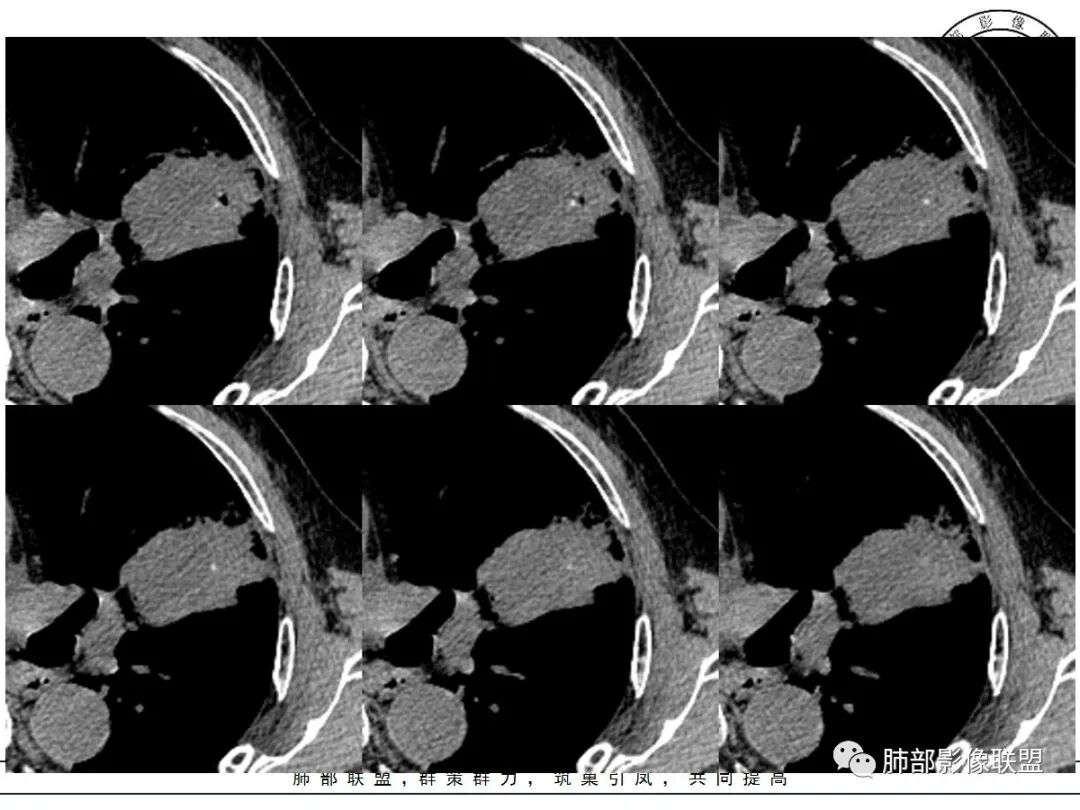

这三个月后的

发了后面这个,就不用纠结了,直接秒了。

大雄:

我只是要告诉大家,不是二元,就是肿瘤,没有什么感染,磨玻璃都没消失。

1、团片状,实行密度区外观整体圆顿,位于上叶尖后段与下舌段区间。局部膨隆,但未见分叶,肿瘤多见。

2、偏心空腔病灶,气腔略呈新月形,壁不规则,腔内结节相对密实,明显强化且不均,支持新生物而非曲菌球等。炎性空洞多有强化环。

3、病变强化较明显,其内隐约显示多发小斑片状无强化灶,可疑边界不清小灶坏死区。病灶内血管影浅淡、模糊不规则。

4、支气管改变:上舌段支气管远段延入部分稍示僵硬。尖后段见分支支气管阻塞,恶性多见。

5、周围磨玻璃,3个月后逐渐转为密实,应符合当初附壁生长为主,且逐渐向实体成分转换。

6、病变长轴平行且受限于胸膜,外围大内带小,符合外朝内发展病变。“腔内结节状明显强化”加之支气管改变有力支持新生物诊断。如此大范围边界不清的磨玻璃影让人浮想联翩。如此大范围病灶,肺门纵隔未见肿大淋巴结也让人意外。